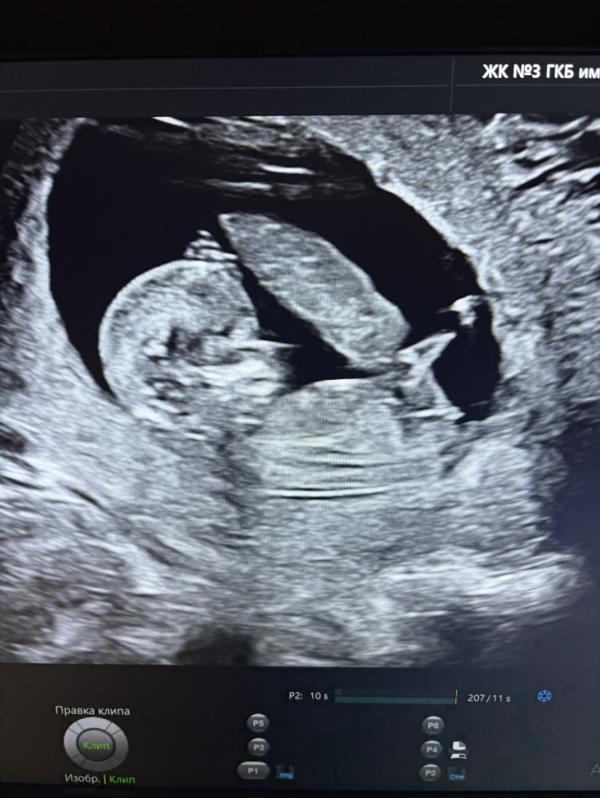

Была на первом скрининге, пол не сказали. Кто-нибудь разбирается?☺️

По фото не скажешь какой пол. Сходите в 16 недель на узи. Там уже будет видно все хорошо

На первом скрининге даже узисты не могут точно пол определить, а вы у мам спрашиваете))

Ну и по фото конечно, не вижу писюна как у мальчика)

Так тут не видно ))) надо чтоб вид был либо снизу либо боком но чтоб прсюн было видно